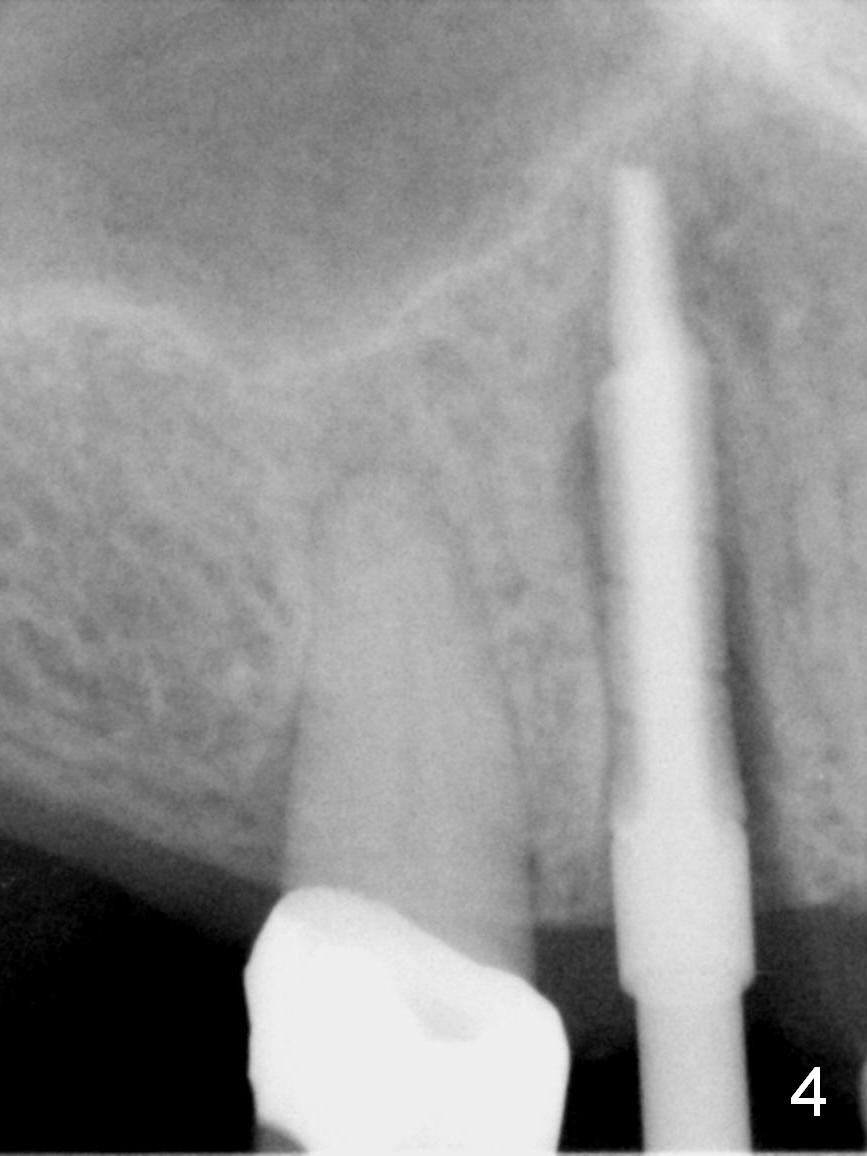

After long discussion, she agrees with extraction and immediate implant. After the extraction, granulation tissue is removed. There is buccal apical fenestration. The socket is treated with Metronidazole. The socket depth is 17 mm, while osteotomy depth is 20 mm (Fig.4). A 4x20 mm tissue-level implant is placed with primary stability (Fig.5,6 I). A short abutment (A) is placed immediately for an immediate provisional. The buccal gap is filled with Osteogen plug. There is no crestal bone loss 3 months postop (Fig.7). The provisional stays in place with occlusal perforation. The gingiva is healthy 5.5 months post cementation (Fig.8).